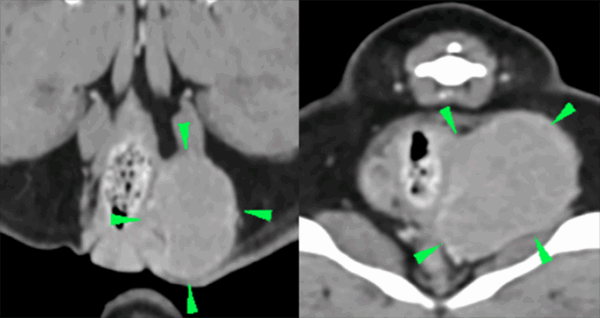

Tras el diagnóstico, y con el fin de completar el estadio clínico del paciente y trazar el plan terapéutico, se realizaron radiografías torácicas de tres posiciones (sin hallazgos fuera de la normalidad), ecografía abdominal (dentro de la normalidad) y estudio TC de tórax (sin hallazgos fuera de la normalidad) y abdomen, donde se evidenció una masa bien definida de 4,5×3,2×3,5 cm en el saco anal izquierdo, ovalada y de márgenes lisos, de atenuación tejido blando y realce homogéneo. La masa comprimía levemente el ano en su aspecto izquierdo (imagen 2). El saco anal derecho se presentaba sin alteraciones. Se observó un mínimo engrosamiento de los linfonodos glúteo y sciático izquierdos comparados con los derechos (con espesores de aproximadamente 3,5 mm). La forma y el tamaño de los linfonodos iliacos eran normales.